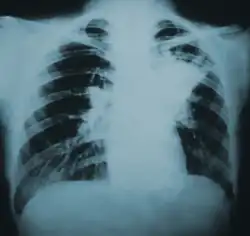

| Lung infiltration in blastomycosis. | |

Blastomycosis manifests as a primary lung infection in about 79% of cases.[8] The onset is relatively slow, and symptoms are suggestive of bacterial pneumonia, often leading to initial treatment with antibacterials. Because the symptoms are variable and nonspecific, blastomycosis is often not even considered in differential diagnosis until antibacterial treatment has failed, unless there are known risk factors or skin lesions.[8] The disease may be misdiagnosed as a carcinoma, leading in some cases to surgical removal of the affected tissue.[19] Upper lung lobes are involved somewhat more frequently than lower lobes.[20] If untreated, many cases progress over months to years to become disseminated blastomycosis.

Blastomycosis in the lungs may present a variety of symptoms, or no symptoms at all.[8] If symptoms are present they may range from mild pneumonia resembling a pneumococcal infection to acute respiratory distress syndrome (ARDS).[8] Common symptoms include fever, chills, headache, coughing, difficulty breathing, chest pain, and malaise.[8] Without treatment, cases may progress to chronic pneumonia or ARDS.[8]

Because the symptoms of blastomycosis resemble those of many other conditions, including tuberculosis and lung cancer, diagnosis is often delayed. In 40% of cases, the diagnosis takes more than a month.[25] A rapid diagnosis can, however, be made based on microscopic examination of sputum samples or samples obtained from a tissue biopsy or bronchoalveolar lavage.[26]